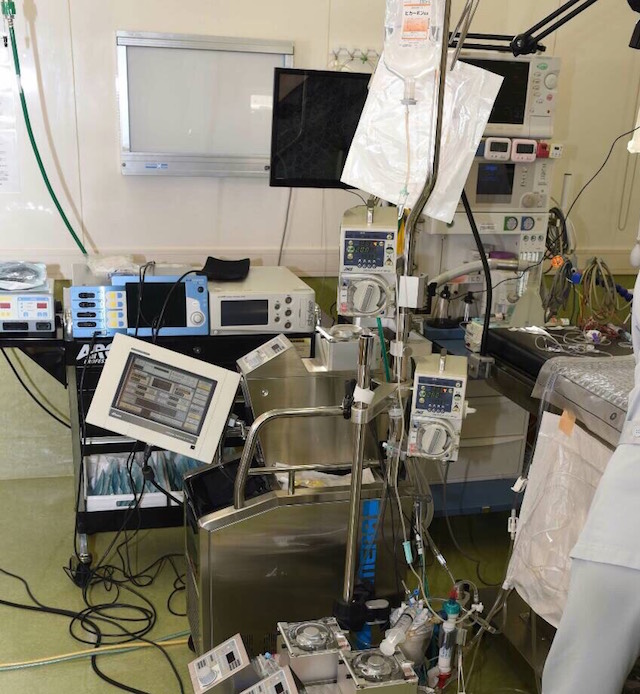

この手術を行うには下記のような大掛かりな機器が必要であり、また、執刀医、助手、麻酔医、体外循環器を操作する技師、周囲のサポートを行うスタッフとの連携が重要になります。

【体外循環器】